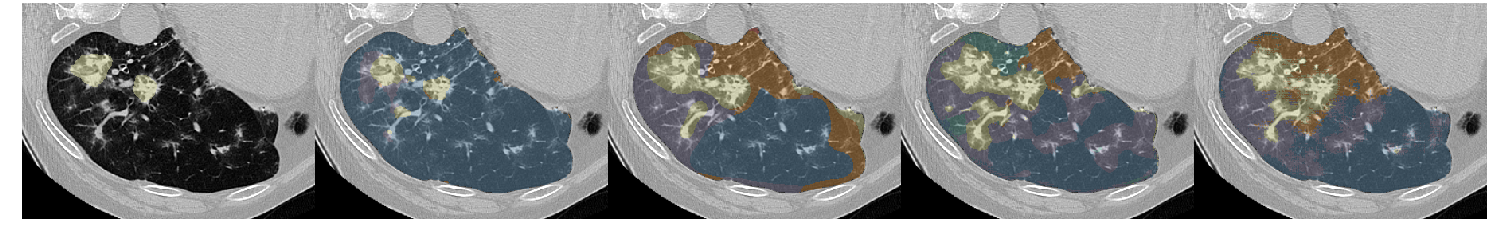

Table III presents a comparison between the proposed network and three previous studies. It has to be noted that all models used the same unsupervised weight (wu=0.1subscript𝑤𝑢0.1w_{u}=0.1) and whenever batch normalization was performed, this was based on batch statistics (instance normalization) since this yielded the best results. Fig. 7 illustrates a few segmentation results for each of the models in Table III.

The first line of the table refers to our previous work [5], which has been converted into a fully convolutional network so it can accept arbitrarily sized images for input. Its low accuracy is probably due to the small receptive field (33×\times33) and the extensive pooling. This architecture was sufficient to describe the local texture of the 32×\times32 single-class patches in [5], but could not capture higher level structure that is present in the whole-lung dataset of this study. The results of the model in Fig. 7 show its noisy output near the lung boundaries or between patterns, where context information could be useful. Segnet [15] and U-net [17] yielded better results, with the latter being slightly faster and substantially more accurate. Both models have a very high number of parameters and large enough receptive fields to capture any relevant information. The superior performance of U-net could be attributed to its skip connections that allow features from the lower scales to directly contribute to its output. Indeed, Fig. 7 illustrates the more detailed results of U-net as opposed to the overly smoothed areas produced by Segnet. Finally, the proposed network yielded the best results, while being faster and having far fewer parameters. The output examples in Fig. 7 indicate that the proposed model manages to keep a better balance between fine details and smooth border among the different classes. Even thought it is really difficult to visually assess the performance of the system for the different classes, there are a few examples in Fig. 7 with wrong classifications on which we can comment. Firstly, parts of the broncho-vascular tree in the third row were recognized as consolidation because of their similar densities, while accentuated terminal bronchial parts, that might be physiological as well, caused the erroneous classification of healthy areas into reticulation, in the first row. Some mistakes however are also attributed in the limited number of annotated classes. For example in row 6, there are emphysematic areas (dark area in the center of the lung) that have been annotated as healthy due to their similar density. Figure 6 shows the confusion matrix of the proposed model. As expected, many of the misclassifications occur between reticulation and honeycombing due to their similar textural appearance. Moreover, healthy tissue is often confused with reticulation probably because of the 2D sections of the bronchovascular tree that could resemble reticular patterns.

Refer to caption

Figure 7: Output examples for the models of Table III. From left to right: Ground Truth, ILD-CNN, Segnet, U-net, Proposed. Each example has a different pattern annotated. From top to bottom: Healthy (Blue), Ground Glass Opacity (Purple), Micronodules (Green), Consolidation (Yellow), Reticulation (Orange) and Honeycombing (Red).